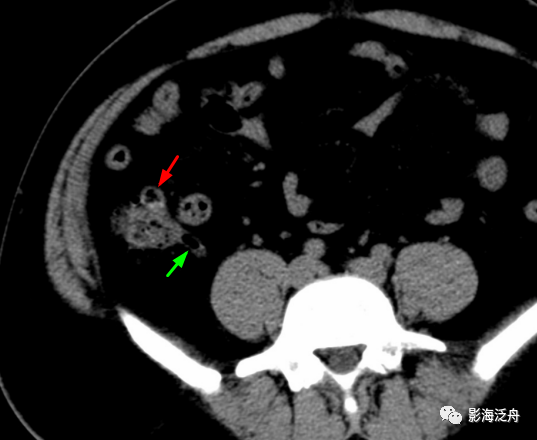

阑尾区局部密度增高,病变周围脂肪间隙模糊,阑尾腔内见高密度粪石影

(3)ct检查:平扫见右下腹阑尾内粪石,阑尾增粗,管壁毛糙,周围脂肪间隙